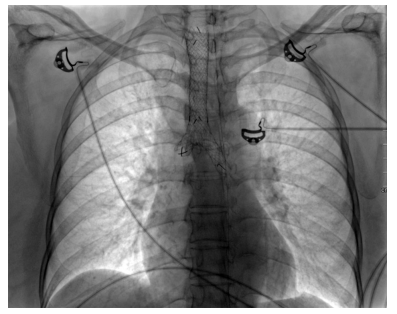

She was doing well for six months; however, she presented to emergency with history of cough, fever and wheeze for 15 days. On evaluation, she had type 2 respiratory failure and needed biphasic positive airway pressure support. Also, she was given high-dose steroids under antibiotics cover. HRCT of the chest showed worsening as expected. There was no improvement with the existing treatment even after three weeks. Patient continued having carbon dioxide retention with high respiratory rate and deterioration of sensorium despite noninvasive ventilation support. She also developed hospital-acquired infection. Discussion with the respiratory team and relatives ensued and decision for tracheal stenting was established (Figures 3 and 4).

Earlier stenting was avoided in view of long segment involvement. Post-procedure, she was put on ventilator and tracheostomized later in view of long-term ventilatory involvement. She was discharged after three weeks of hospital stay and later she suffered from post-procedure complications like tracheostomy site ulcer and its bleeding, subcutaneous emphysema and difficulty regaining activities of daily living. She was readmitted after a month with worsening of breathlessness and fever and was bound to have bilateral pneumonia. This time, she succumbed in view of sepsis and related acute kidney injury.